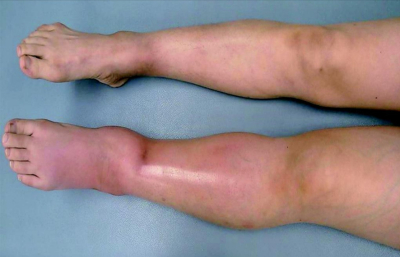

意識は清明。身長 158 cm、体重 45 kg。体温 39.9 ℃。脈拍 100/分、整。血圧 96/60 mmHg。口唇粘膜にアフタ性口内炎を認める。心音と呼吸音とに異常を認めない。腹部は平坦、軟で、肝・脾を触知しない。表在リンパ節の腫大を認めない。左下腿から足関節部にかけて軽度の熱感を認める。四肢関節に腫脹や圧痛を認めない。

尿所見:蛋白(−)、潜血(−)、白血球3+。検査所見:赤沈 73mm/1時間。血液所見:赤血球 354万、Hb 9.1g/dL、Ht 28%、白血球 8,400(桿状核好中球 5%、分葉核好中球 67%、好酸球 1%、単球 10%、リンパ球 17%)、血小板 36万、PT-INR 1.2(基準 0.9〜1.1)、APTT 27.8秒(基準対照 32.2)、フィブリノゲン 525 mg/dL(基準 186〜355)、Dダイマー 4.1 μg/mL(基準1.0以下)。血液生化学所見:総蛋白7.3g/dL、アルブミン 2.3 g/dL、AST 14 U/L、ALT 11 U/L、LD 144 U/L(基準 120〜245)、尿素窒素 9.1 mg/dL、クレアチニン 0.4 mg/dL、CK 51 U/L(基準 30〜140)。CRP 12 mg/dL。両下肢の写真及び鼠径部の造影CTを別に示す。